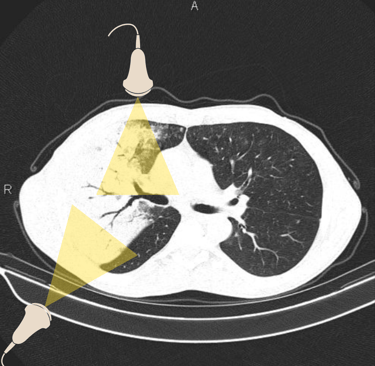

Figura 2. Veja como é possível diagnosticar essa extensa pneumonia utilizando os pontos do protocolo BLUE. Tomografia retirada de https://radiopaedia.org/cases/air-bronchogram-in-pneumonia#image-54184430, e editada pelo autor.

Essa pergunta pode ser respondida com o 7º princípio do US pulmonar, descrito por Lichtenstein: Distúrbios agudos possuem localização superficial e extensa (figura 2). Pensa comigo, nosso paciente está em insuficiência respiratória aguda, logo, o que quer que esteja causando uma apresentação clínica tão dramática, deve ser facilmente visível sem que o examinador precise "procurar demais".